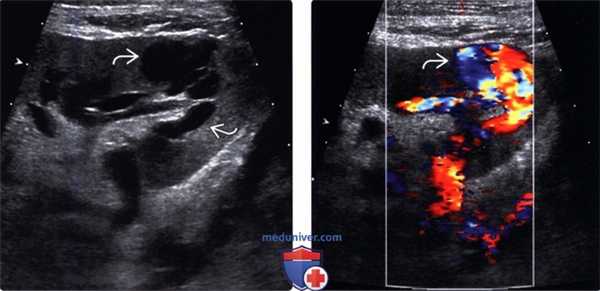

(Левый) Допплерографический срез через анастомоз почечной артерии у пациента с острым повреждением почки через год после трансплантации от умершего донора. В анастомозе визуализируется цветовой дефект наложения с пиковыми скоростями, превышающими 385 см/с.

(Правый) При цифровой субтракционной ангиографии у этого же пациента подтвержден выраженный стеноз (>90%) в области анастомоза S3, скорректированный путем ангиопластики.